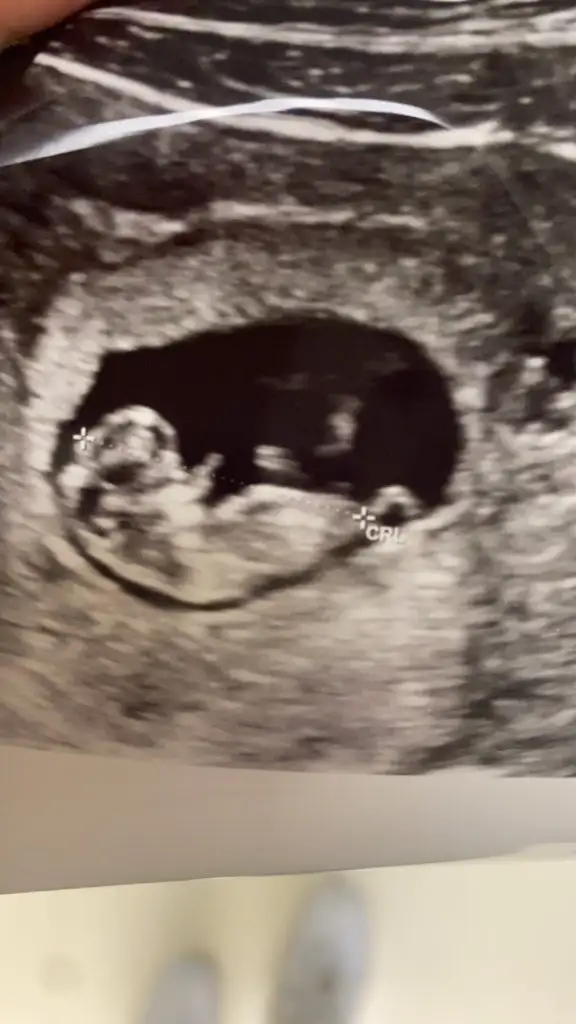

belli olmuyor8+0 karından tahminde bulunurmusunuz![]()